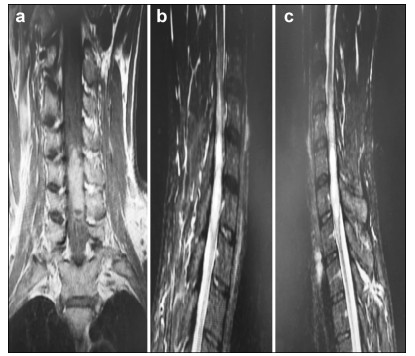

A 35-year-old male presented with the chief complaint of pain in the neck and back for 6 months. There was no weakness or numbness in the upper and lower limbs. MRI of the spine revealed an intramedullary mass at C5-T1. We advised resection. Because of cervical cord involvement, he underwent GTR under awake anesthesia (AAA), after providing informed consent. Intraoperatively, he was instructed to move his upper and lower limbs during the awake cycle of AAA. He was also not extubated during the awake cycle. All commands were followed. As the language center was not in the surgical field, no speech assessment was required. Sensory functions were also minimally assessed by lightly touching the upper and lower limbs and then asking the patient to raise his thumb if he perceived sensation. Frozen section confirmed the diagnosis of ependymoma, and GTR was performed successfully. His symptoms were completely relieved, and no motor deficits were observed at 3 and 6 months of follow up.

Preoperative and postoperative MR images of Case 2 are shown in Figure 3 and Figure 4, respectively.

| Figure 3 a–c. Preoperative MR images of Case 2. |